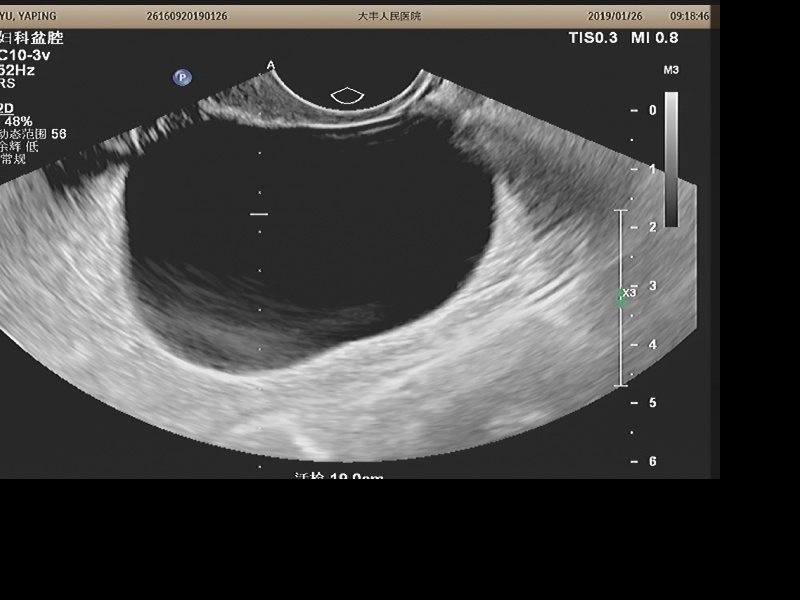

手术前卵巢囊肿